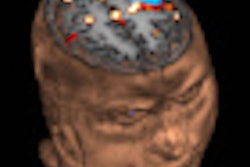

French researchers have found good agreement between functional MRI (fMRI) and FDG-PET in assessing brain function in comatose patients. Their research indicates that fMRI potentially could help guide treatment of these individuals.

fMRI scans, based in part on the measurement of signals induced by the blood-oxygen-level dependent (BOLD) concentration in the cerebral vasculature, were performed on a 1.5-tesla magnet (Magnetom Avanto, Siemens Healthcare, Erlangen, Germany) with an eight-channel head coil. Stimuli were presented using a system designed for fMRI (IFIS-SA, Invivo, Orlando, FL). Patients also were given headphones for auditory stimuli and to protect them from scanner noise. In addition, an LCD screen was positioned over the head coil in front of a patient's eyes for visual stimuli.

fMRI's advantage is its noninvasive ability to provide information about morphological brain lesions induced by a trauma or lack of oxygen, as well as brain functions, such as cortical integration of vision, audition, and sensitivity. Compared to evoked potential, fMRI can directly visualize cortical activation with anatomical localization in both cerebral hemispheres.